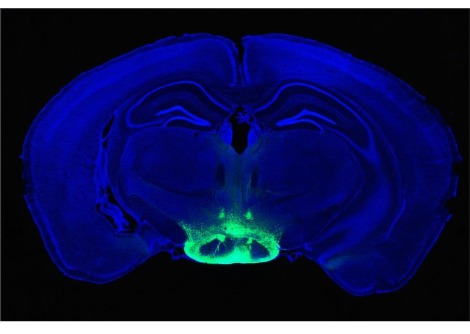

أدخل الباحثون مصفوفتين من الأقطاب الكهربائية المربعة، بعرض 3.2 ملم، في جزء من الدماغ يتحكم في الحركة . عندما طلبوا من الرجل أن يحاول تحريك يديه وقدميه ورأسه وعينيه ، لم تكن الإشارات العصبية متسقة بما يكفي للإجابة على أسئلة بنعم أو لا، كما يقول أوجوال تشودري، مهندس الطب الحيوي وخبير التكنولوجيا العصبية في الجمعية الألمانية غير الربحية ALS VOICE .